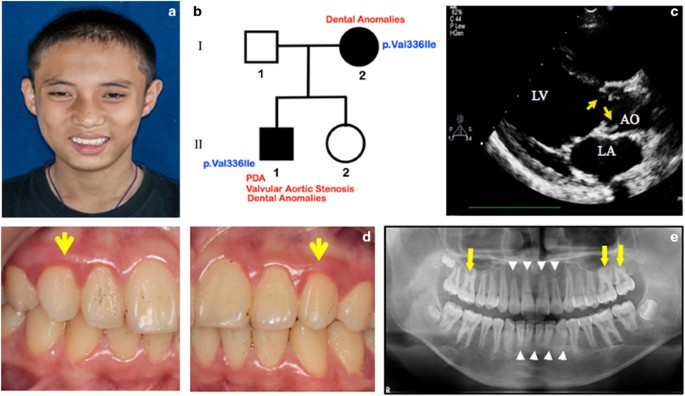

TFAP2B mutation and dental anomalies | Journal of Human Genetics